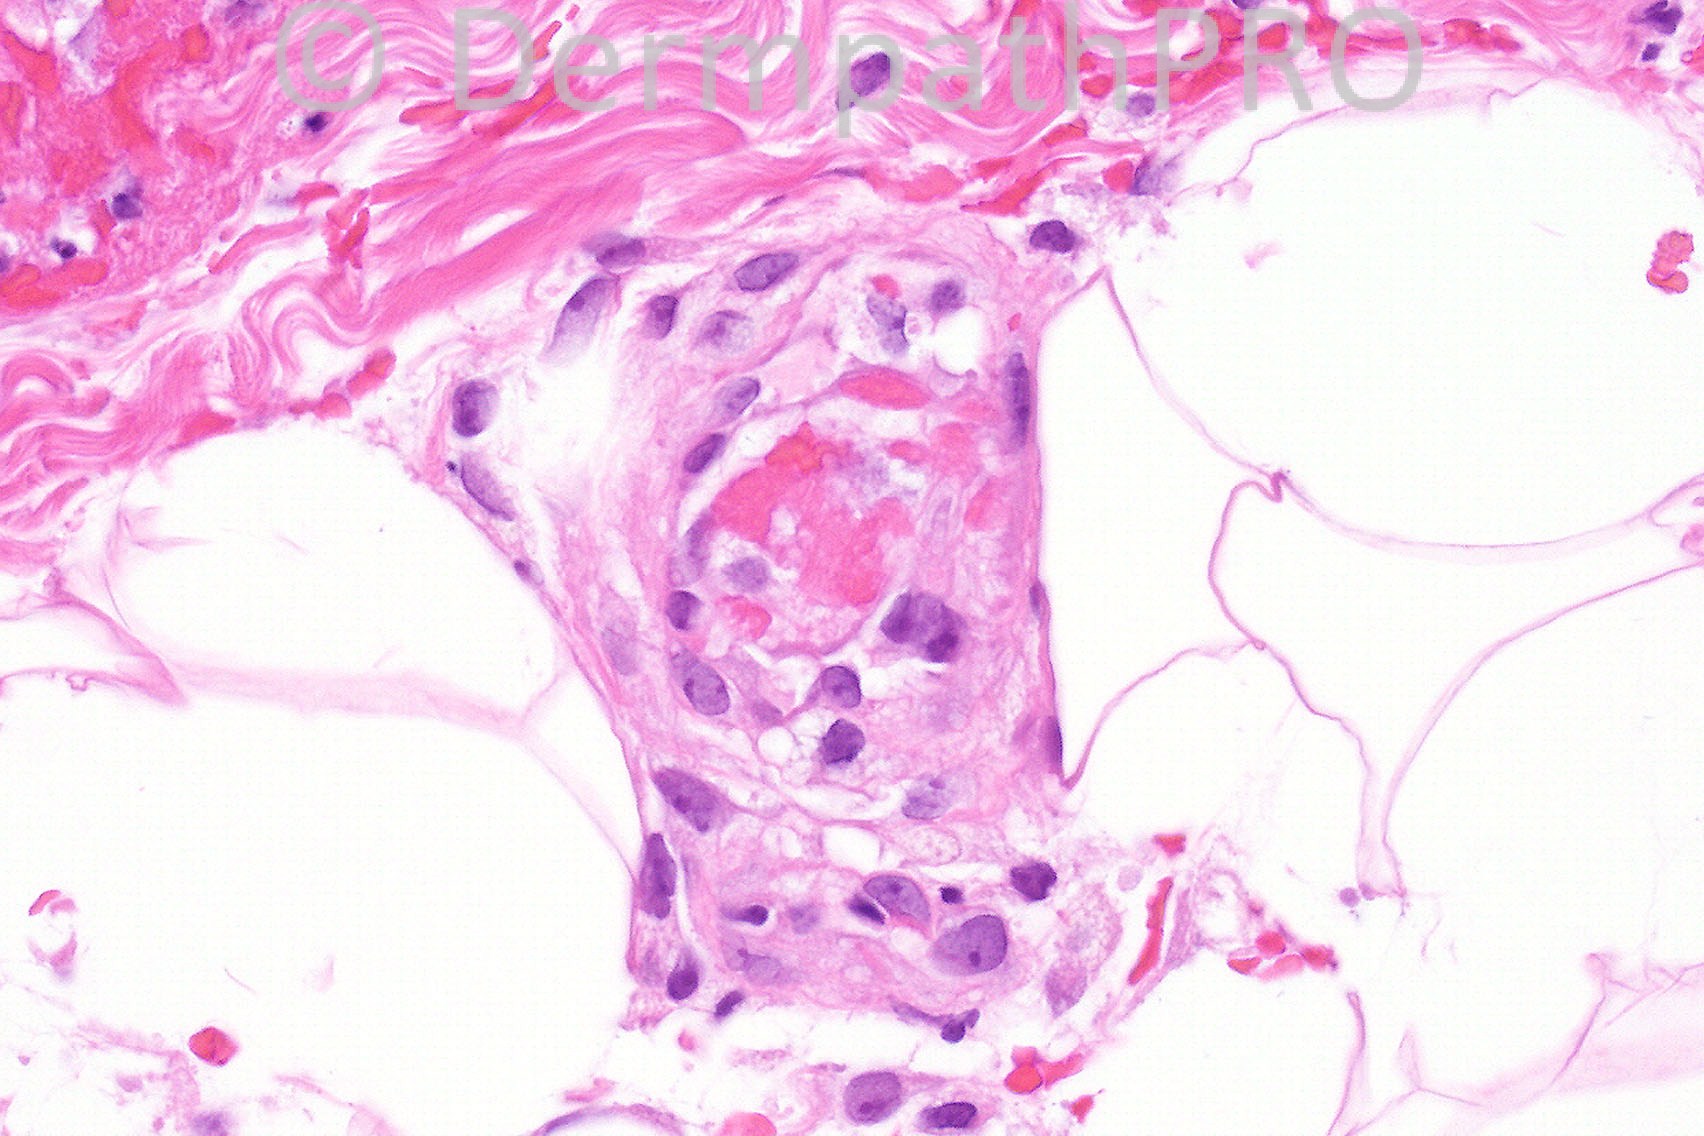

Female aged 28 years with widespread purpuric lesions clinically thought to represent polyarteritis nodosa or Wegener's granulomatosis.